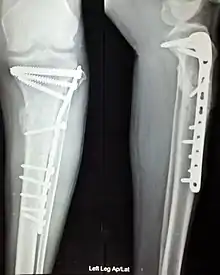

Open Reduction Internal Fixation (ORIF) involves the implementation of implants to guide the healing process of a bone, as well as the open reduction, or setting, of the bone. Open reduction refers to open surgery to set bones, as is necessary for some fractures. Internal fixation refers to fixation of screws and/or plates, intramedullary rods and other devices to enable or facilitate healing. Rigid fixation prevents micro-motion across lines of fracture to enable healing and prevent infection, which happens when implants such as plates (e.g. dynamic compression plate) are used. ORIF techniques often are used in cases involving serious fractures such as comminuted or displaced fractures or, in cases where the bone otherwise would not heal correctly with casting or splinting alone.

Various techniques of minimally invasive surgery for internal fixation of bones have been reported. The treatment of fractures of the distal third of the tibia has evolved with the development of improved imaging and surgical techniques.[5]

Additional images